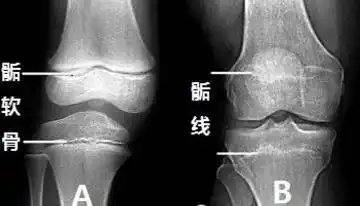

下肢骨为什么会增长?